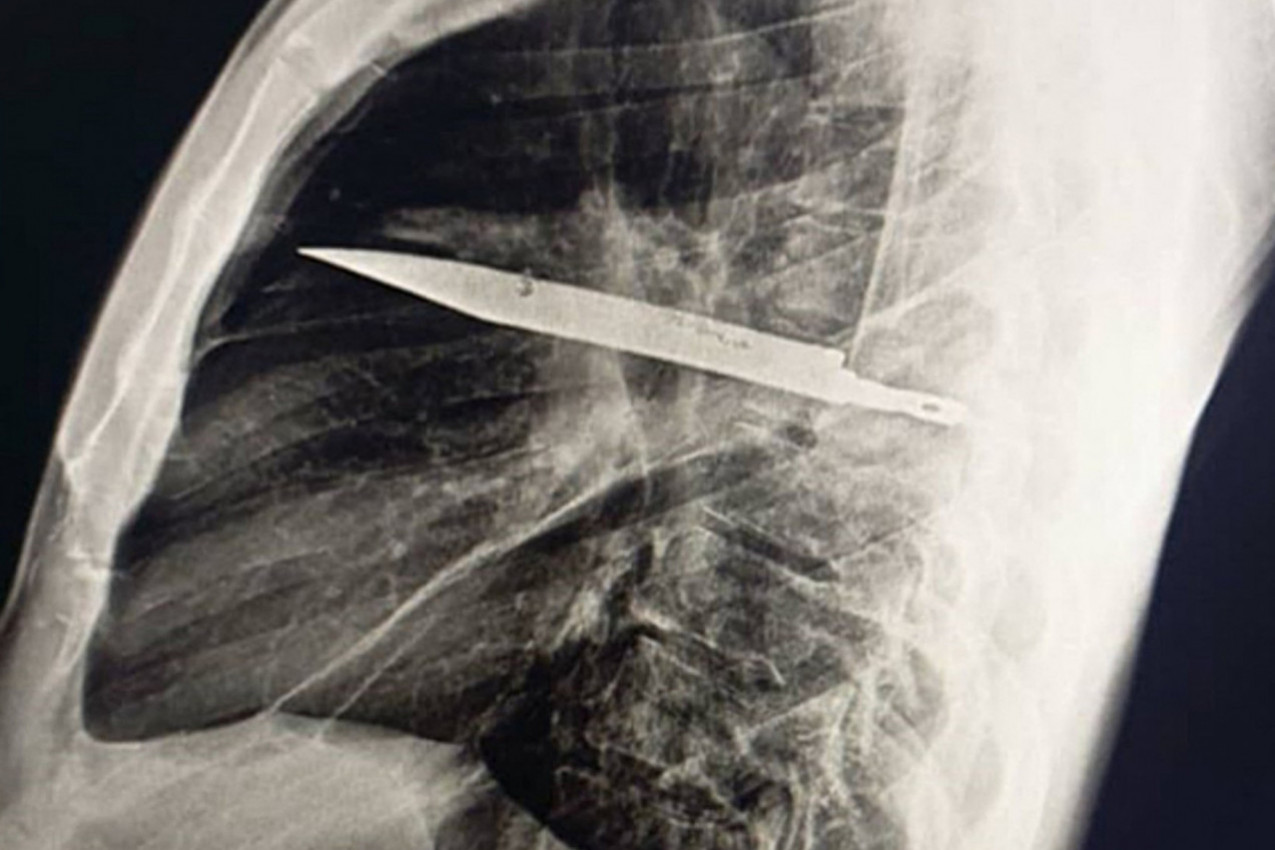

Kada je muškarac konačno potražio pomoć lekara zbog gnoja, rendgenski snimak je otkrio "zadržani metalni objekat" unutar njegovog grudnog koša. Nož je ušao kroz lopaticu i bio je okružen "gnojem i nekroznim tkivom".

Jam Press/Journal of Surgical Case Reports / MEGA / The Mega Agency / Profimedia